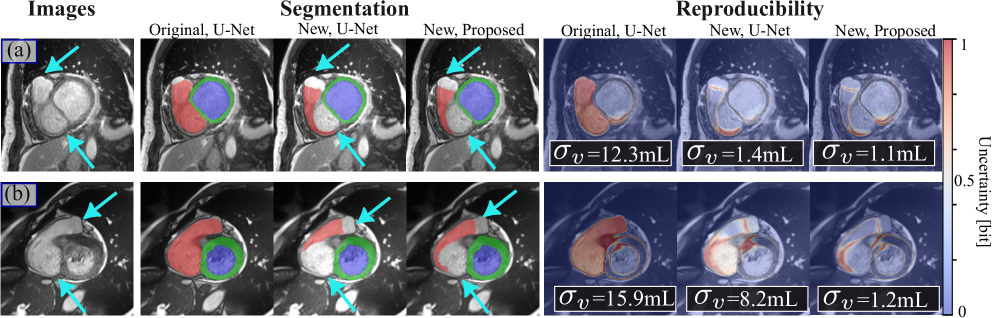

Refer to caption

Figure 5: Examples of RVOT segmentation and reproducibility. High uncertainty indicates strong disagreement among different ensemble models. (a) Models trained with the original labels are uncertain on basal slices with both the valve and atria (cyan arrows) inplane. (b) The reproducibility is largely improved by the new annotations, and further reduced by the proposed method.

All methods have a volume variance that peaked at a relatively low value (<5absent5<5< 5 ml), especially at ES. However, we observe that the U-Nets trained with the original annotations have a longer tail than networks trained with the new annotations. The proposed method exhibits the highest reproducibility with a sharp peak. Fig. 5 (a) is a basal slice that covers the partial atrium and valve (cyan arrows) on the image plane. In this slice, we observe that the networks trained with the original annotations are highly uncertain, resulting in a volume SD of 12.312.312.312.3 ml. In contrast, the networks trained with the new annotations successfully delineate the RVOT and have a reduced SD of 1.11.4similar-to1.11.41.1\sim 1.41.1 ∼ 1.4 mL. In Fig. 5 (b), we show a case in which the vanilla U-Nets can have low reproducibility because the RVOT and atrium are not distinguishable, with σv=8.2subscript𝜎𝑣8.2\sigma_{v}=8.2italic_σ start_POSTSUBSCRIPT italic_v end_POSTSUBSCRIPT = 8.2 mL. In comparison, our proposed method reduces σvsubscript𝜎𝑣\sigma_{v}italic_σ start_POSTSUBSCRIPT italic_v end_POSTSUBSCRIPT to 1.21.21.21.2 mL. The results suggest that consistent annotation and loss-of-tracking can greatly improve reproducibility when segmenting difficult regions like the RV base.